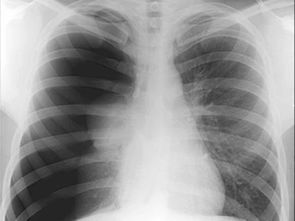

医生告诉他,这是一种叫做气胸的疾病。气胸是指气体在胸膜腔内积聚,导致肺部部分或完全塌陷的情况。听到这个消息时,他的心猛地一沉,脑海中涌现出无数疑问:为什么会发生这种事?接下来该怎么办?

为了更好地了解自己的病情,他开始查阅大量资料。气胸可以分为自发性气胸和创伤性气胸两大类。自发性气胸通常发生在没有明显外伤的情况下,可能与肺部疾病、先天性因素或者身高体重比例有关。而创伤性气胸则多由外部伤害引起,比如车祸或者刺伤。